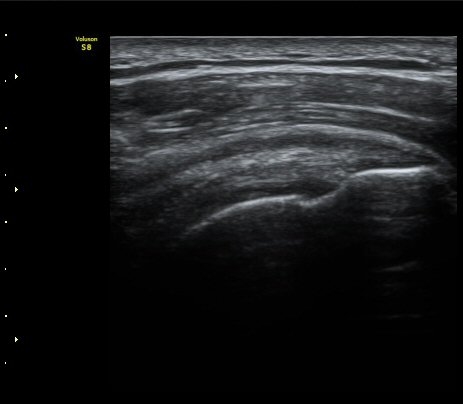

±Ø»ó°Ç³»Ãø Á¾´Ü¸é°Ë»ç¿¡¼­ ±Ø»ê°Ç ºÎÂøºÎÀÇ  ÀÛÀº ÆÄ¿­°ú Á¡¾×³¶ ºÎÁ¾ÀÌ °üÂûµÊ(±×¸² 2, 3).

±Ø»ó°Ç ¿ÜÃø Á¾´Ü¸é°Ë»ç ½Ã Á¡¾×³¶ ºÎÁ¾ÀÌ °üÂûµÊ(±×¸² 4).

±Ø»ó°Ç ±ÙÀ§ºÎ ±Ø»ó°Ç ³»ÃøÀÇ Àú¿¡ÄÚ ºÎÁ¾°ú Á¡¾×³¶ ºÎÁ¾ÀÌ °üÂûµÊ(±×¸² 5).

±Ø»ó°Ç ¿øÀ§ºÎ ±Ø»ó°Ç ºÎÂøºÎ ÀÛÀº ÆÄ¿­ÀÌ °üÂûµÊ(±×¸² 6).

ŽÃËÀÚ¸¦ °ßºÀ ¿ÜÃø¿¡ ´ë°í ÆÈÀ» ¿ÜÀüÇϸ鼭 ´ë°áÀý°ú °ßºÀÀÇ Ãæµ¹À» °üÂûÇÏ´Ï °ßºÀ¿ÜÃø¿¡

¼ö¾×ÀÌ Àú·ùµÇ¾î ¿ÜÃø Ãæµ¹ÁõÈıºÀÌ È®ÀεǾú´Ù(÷ºÎ ÆÄÀÏ 1).